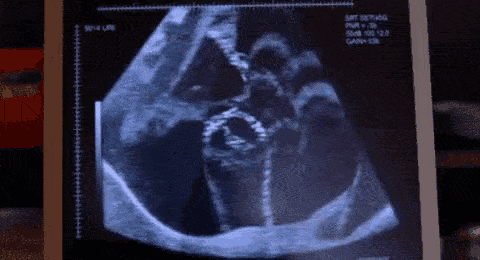

¿Quieres ver cómo funciona? Este vídeo te muestra exactamente cómo el ajuste de Profundidad y Ganancia transforma la imagen en tiempo real.